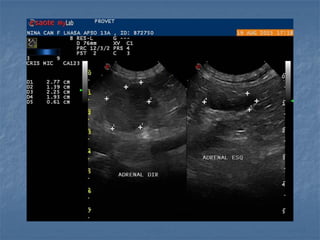

 Em cães

 Formato (parece o formato do cão!):

- Esquerda tem formato de amendoim (alongada)

- Direita tem formato de vírgula

 Ecogenicidade: hipoecoica em relação a gordura

adjacente, com cortical e medular distintas

 Dimensões (cães):

- 2,0 a 3,0cm x 0,5cm

- Idosos até 0,74cm

- máximo diâmetro no

pólo caudal (melhor

sensibilidade e

especificidade)

Barthez et al.,1998

 Em cães Formato (parece o formato do cão!): - Esquerda tem formato de amendoim (alongada) - Direita tem formato de vírgula  Ecogenicidade: hipoecoica em relação a gordura adjacente, com cortical e medular distintas

 Dimensões (cães): -2,0 a 3,0cm x 0,5cm - Idosos até 0,74cm - máximo diâmetro no pólo caudal (melhor sensibilidade e especificidade) Barthez et al.,1998